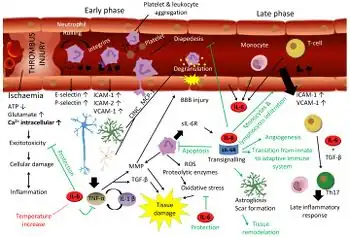

| CT scan of the brain showing a prior right-sided ischemic stroke from blockage of an artery. Changes on a CT may not be visible early on.[1] | |

The main risk factor for stroke is high blood pressure.[6] Other risk factors include tobacco smoking, obesity, high blood cholesterol, diabetes mellitus, a previous TIA, end-stage kidney disease, and atrial fibrillation.[2][6][7] An ischemic stroke is typically caused by blockage of a blood vessel, though there are also less common causes.[12][13][14] A hemorrhagic stroke is caused by either bleeding directly into the brain or into the space between the brain's membranes.[12][15] Bleeding may occur due to a ruptured brain aneurysm.[12] Diagnosis is typically based on a physical exam and supported by medical imaging such as a CT scan or MRI scan.[8] A CT scan can rule out bleeding, but may not necessarily rule out ischemia, which early on typically does not show up on a CT scan.[9] Other tests such as an electrocardiogram (ECG) and blood tests are done to determine risk factors and rule out other possible causes.[8] Low blood sugar may cause similar symptoms.[8]

For diagnosing ischemic (blockage) stroke in the emergency setting:[64]

- CT scans (without contrast enhancements)

- sensitivity= 16% (less than 10% within first 3 hours of symptom onset)

- specificity= 96%

CT scans may not detect an ischemic stroke, especially if it is small, of recent onset, or in the brainstem or cerebellum areas. A CT scan is more to rule out certain stroke mimics and detect bleeding.[9]